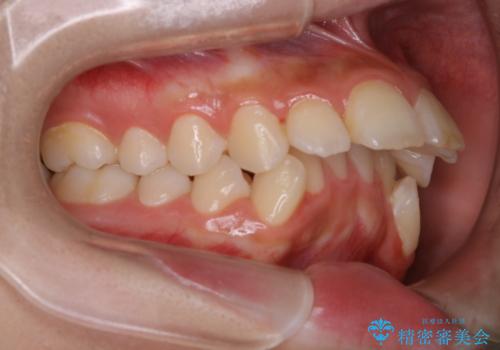

出っ歯と深い噛み合わせ:抜歯矯正で口元スッキリ!

- 出っ歯が気になるとご相談にいらした方です。抜歯して歯を並べました。深かった噛み合わせも改善させることが出来ました。

噛み合わせが元々深い方は一般的に噛む力が強く、治療に時間がかかる傾向にあります。治療前の想定よりも短期間でスムーズに治療を終える事ができ、大変喜んでいただけました。リテーナーによる保定もしっかり行っていただいており、後戻りなく快適にすごして頂けているとのことです。